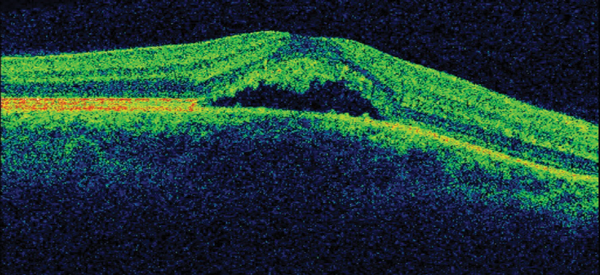

On ocular examination, visual acuity was 6/6 in both eyes (BE). Anterior segment and intraocular pressure were normal. Fundal assessment revealed a characteristic lesion in the macular area in the right eye shown in Figure 1a. Figure 1b shows the corresponding optical coherence tomography (OCT) image of the lesion. Left eye (LE) fundus was unremarkable.

Figure 1a: RE funduscopy at presentation.

1. Figure 1a shows an area of retinal pigment epithelium changes associated to a surrounding well-defined round area of serous macular elevation. The fluid is occupying the space between the photoreceptor layer above and retinal pigment epithelium (RPE) below called subretinal space. Given the young age of the patient, the unremarkable medical history but the underlying stress, and the clinical features the most likely diagnosis would be central serous retinopathy (CSR). The most accepted current theory to explain the pathophysiology of CSR is a combined dysfunction of both choroid and RPE resulting in focal choroidal hyperpermeability and eventual accumulation of fluid in the subretinal space.